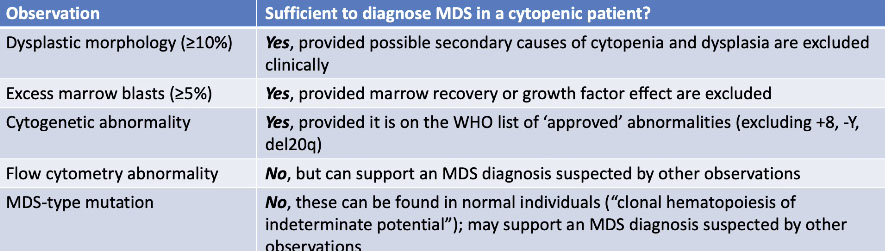

MDS diagnosis [3], must rigorously exclude secondary causes if diagnosing by morphology, diagnosing MDS in a vacuum is reckless

MDS diagnosis and IPSS-R [3]

Figure 6. Hematopathology alphabet soup: a quick comparison. With CHIP, ICUS, CCUS, and MDS. From Albert C. Integrating NGS into the cytopenia workup. CAP Today; May 2022.

MDS diagnostic algorithm tree. From Albert C. Integrating NGS into the cytopenia workup. CAP Today; May 2022.